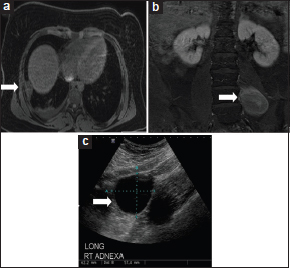

On physical examination, she had decreased air entry in the right lower lung base. Laboratory workup, including complete blood count, comprehensive metabolic panel, uric acid, and lactate dehydrogenase, was within normal limits. A chest X-ray showed pleural thickening along the lateral right lower lung base. Magnetic resonance imaging (MRI) of the chest, abdomen, and pelvis with contrast showed a 5.5 cm × 3.7 cm × 1.7 cm sharply demarcated pleural-based mass adjacent to the right sixth rib and a left mid-lumbar mass posterior and contiguous with the psoas muscle measuring 2.2 cm × 5 cm × 0.6 cm [Figure 2]a] and [Figure 2]b]. A small right pleural effusion with adjacent right basilar atelectasis was also noted. Imaging also revealed a left paraspinal mass in the lumbar region and an ovarian cyst in the right ovary. A full-body positron emission tomography scan demonstrated a mildly hypermetabolic lesion in the lower right pleura (standardized uptake value of 2.8). A computerized tomography scan-guided needle biopsy was nondiagnostic, and hence, she underwent a right thoracotomy with an en bloc resection of the right pleural mass and the adjacent sixth rib. The tumor was 5.8 cm in the longest dimension with no involvement of the lung or the rib. Histologically, the mass was encapsulated and composed of uniform spindle cells arranged in sheets and fascicles with alternating areas of relative hyper- and hypocellularity [Figure 3]a]. Mean mitotic count was 5/10 high-power field. Immunohistochemical studies (IHC) showed diffuse staining with TLE1, vimentin, and BCL 2 with focal EMA, CK AE1/AE3, CAM 5.2, CK7, and SMA. CD34, S100, ALK-1, p53, and HMB45 were negative [Figure 3]b-d]. Ki67 was moderately increased. Cytogenetic testing by FISH was positive for SYT (18q11) translocation. These findings were diagnostic of a monophasic SS arising from the pleura. Finally, the tumor was staged and graded as Intergroup Rhabdomyosarcoma Study Group, Group III, Stage III (T2b, N0, M0), Pediatric Oncology Group Grade III (high grade), and French Federation of Cancer Centers Sarcoma Group (FNCLCC) Grade II.

| Figure 2 Radiographic images of all three tumors (white arrows) in the patient. (a) Computed tomography scan of the chest showing primary pleural synovial sarcoma. (b) Magnetic resonance imaging of the spine showing left lumbar ganglioneuroblastoma. (c) Right paraovarian cystadenoma

A computerized tomography-guided biopsy of the left lumbar soft-tissue mass revealed it to be a ganglioneuroma. Urine vanillylmandelic acid and homovanillic acid were within normal limits. A pelvic ultrasound (US) showed a paraovarian cyst measuring approximately 4.9 cm × 4.1 cm × 3.5 cm. It was followed overtime with a pelvic US every 6 months. Following surgical resection of the pleural mass, she received therapy as per Children's Oncology Group protocol ARST0332. She was given 6 cycles of ifosfamide (9 g/m2/cycle) and doxorubicin (75 mg/m2/cycle). She received a total of 55.8 Gray (Gy) in 1.8 Gy fractions of external beam radiation therapy to the right chest wall which was started 4 weeks after the first dose of chemotherapy. She completed the last cycle of chemotherapy in January 2014. Surveillance scans with MRI chest, abdomen, and pelvis every 6 months have revealed no local or systemic signs of relapse with a stable size of the ganglioneuroma. In August 2014, she developed right lower quadrant pain. Pelvic US was concerning for interval increase in the size of the paraovarian cyst (6.2 cm × 5.7 cm × 6 cm) with possible torsion of the right ovary [Figure 2]c]. She underwent right paraovarian cystectomy. Biopsy of the cyst was consistent with a serous cystadenoma. Due to the synchronous occurrence of two tumors at a young age and a significant family history of solid tumors, she underwent a genetic workup for hereditary CPS. Next-generation sequencing of an 18 gene panel (EPCAM, FH, FLON, MET, MITF, MLH1, MSH6, PMS2, PTEN, SDHA, SDHB, SDHC, SDHD, TP53, TSC1, TSC2, and VHL) detected a novel germline missense variant of unknown significance in the MET gene NM_001127500.2(MET):c.623A>G (p. Asp208Gly). At present, the patient remains in remission 3.5 years after completion of therapy.